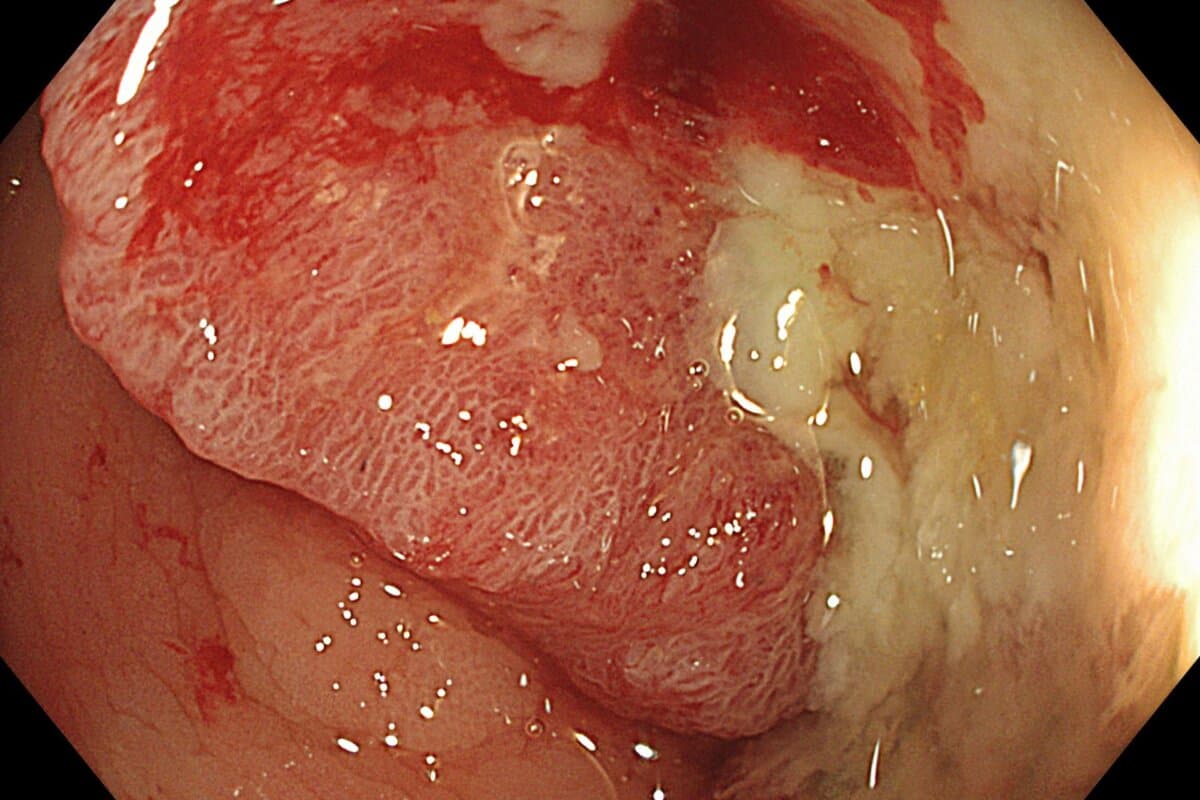

Zwei neue Tests zur Früherkennung des kolorektalen Karzinoms

Zwei Studien haben nichtinvasive Tests vorgestellt, die künftig die Darmkrebsvorsorge zumindest ergänzen könnten. Die erste neue Option, ein Bluttest, könnte von manchen Patienten dabei besser angenommen werden als eine Koloskopie. Der zweite, ein DNA-basierter Stuhltest, übertrifft die Sensitivität des bisher verwendeten Stuhltests FIT bei der Erkennung von kolorektalen Karzinomen deutlich.

Die beiden Tests detektieren DNA-Marker, die typisch für kolorektale Karzinome sind. Sie konnten kolorektale Tumoren mit einer Sensitivität von 83 Prozent (Bluttest) und 93,9 Prozent (Stuhltest) aufspüren. Falsch negative Ergebnisse wurden bei 10,4 (Bluttest) bzw. 7,4 (Stuhltest) Prozent der Personen festgestellt. Nachholbedarf in der Detektion haben beide neue Tests im Vergleich zur Koloskopie bei präkanzerösen Läsionen.